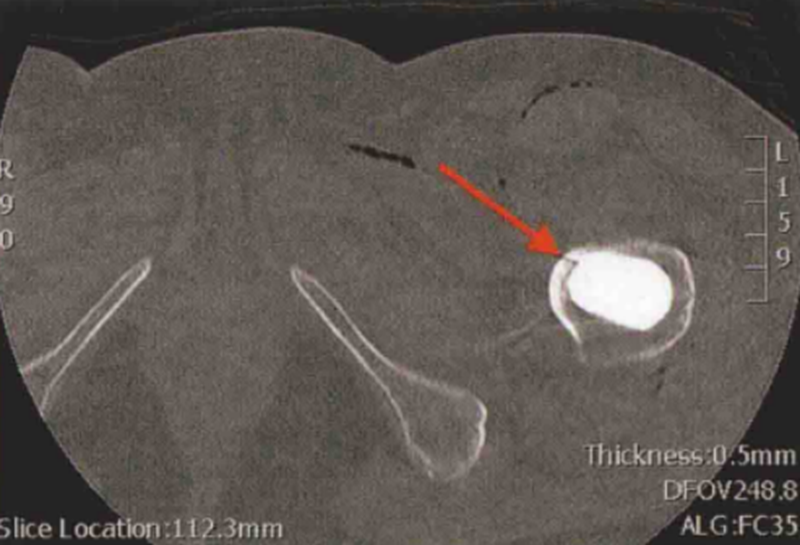

术后常规X线检查显示股骨近端可疑无移位骨折(图1和图2)。CT扫描证实了骨折的存在,且已对假体柄的稳定性造成了影响(图3)。

图3 CT扫描轴位片提示左侧股骨近端无移位假体周围骨折